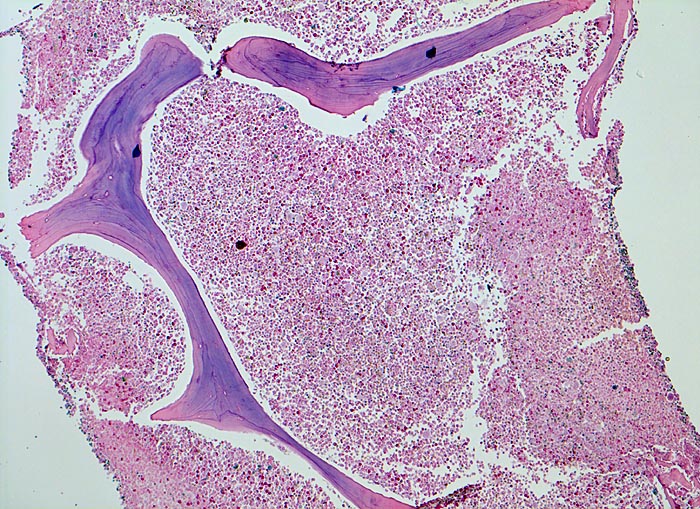

In der chronischen Phase zeigt das Knochenmark eine Hyperzellularität, welche auf eine Vermehrung der neutrophilen Granulozyten und deren Vorläufer zurückzuführen ist. Der paratrabekuläre Streifen unreifer Granulozyten kann verbreitert sein von normal 2-3 Zellschichten auf 5-10 Zellschichten. Blasten machen weniger als 5% der Knochenmarkzellen aus. Eine Blastenzahl von mehr als 10% deutet auf eine Transformation in ein akzeleriertes Stadium und von mehr als 20% entspricht einer Blastenkrise mit Transformation in eine akute Leukämie. Die Megakaryozyten sind typischerweise kleiner als normal, haben hypolobierte Kerne und sind bei 40-50% der Patienten vermehrt. Der Prozentanteil der erythroiden Vorstufen ist gewöhnlich vermindert (G:E Ratio >5:1. Die initiale Knochenmarkbiopsie zeigt bei 40% der Patienten eine Vermehrung von Reticulinfasern assoziiert mit einer erhöhten Anzahl Megakaryozyten. Das Ziel der histologischen Untersuchung des Knochenmarks besteht darin, den Anteil an Blasten im Knochenmark und damit das Stadium der Erkrankung festzulegen. Bis zu einem Blastengehalt von weniger als 10% der kernhaltigen Zellen spricht man von einer chronischen Phase, zwischen 10 und 20% von einer akzelerierten Phase und bei über 20% liegt eine akute Leukämie vor.

• Fast 100% Zellularität des blutbildenden Marks (praktisch keine Fettzellen, sogenanntes "packed marrow").

• Stark vermehrte, ausreifende Myelopoese.

• Der paratrabekuläre Saum unreifer myeloischer Zellen ist verdickt auf 5 bis 6 Zellen.

• Verdrängung der Erythropoese.

• In Gruppen liegende vermehrte nacktkernige (= kein Zytoplasma) verkleinerte Mikromegakaryozyten mit hypolobierten Kernen.